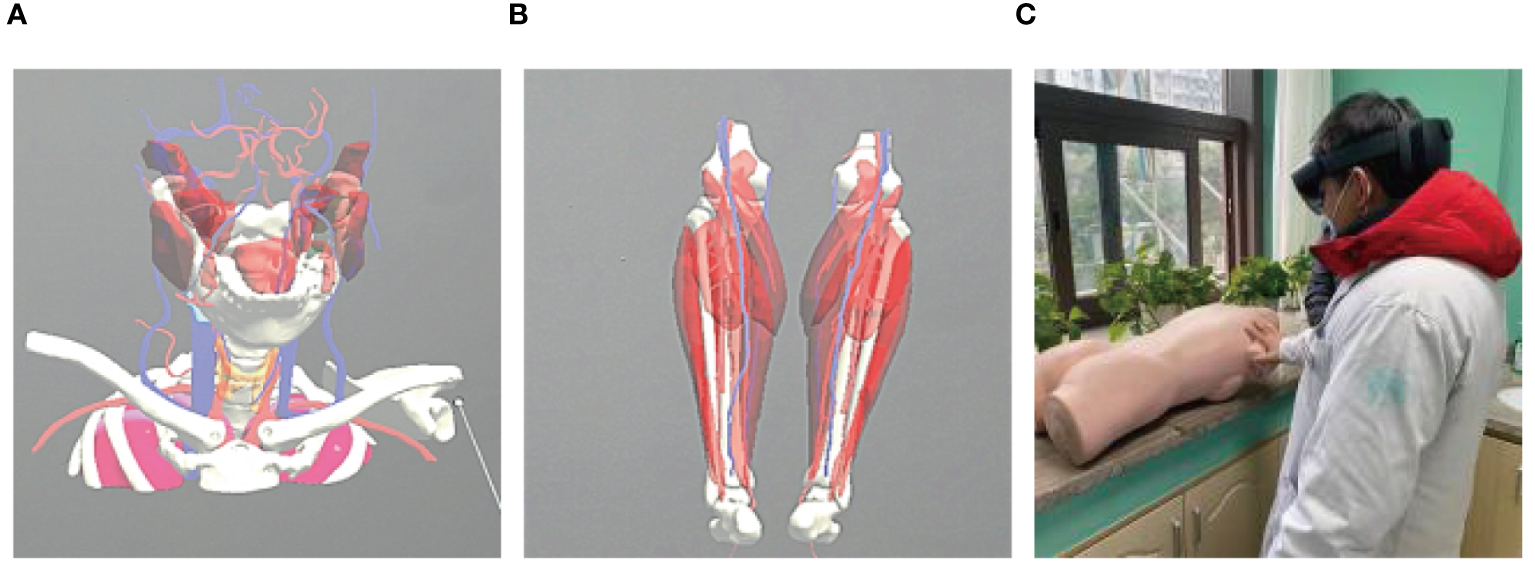

A 56-year-old female underwent surgery for ameloblastoma in the left mandible 2 years previously. Specialist examination revealed that the patient had swelling on the left face and neoplasm in the area surrounding the left mandibular angle and ramus, approximately 5.0 × 4.0 cm measuring in size. The patient also had a mild limitation in mouth opening, and 36, 37, and 38 were not detected in the oral cavity. According to the patient’s previous medical records and consultation report from the pathology department of our hospital, the pathological diagnosis of the patient was confirmed as ameloblastoma (Figure 1). The patient was diagnosed with ameloblastoma upon admission and scheduled to undergo partial mandibular resection and fibular osteocutaneous flap repair. She underwent CTA examination of the maxillofacial and the left calf prior to surgery. The obtained CTA data were imported into a software workstation for 3D reconstruction and subsequently downloaded onto a holographic display (Figures 2, 3). During the operation, the left calf was automatically positioned according to the holographic display, and the perforator vessels were dissected in real-time (Figure 4). Fibular osteocutaneous flaps were prepared to repair the mandible, and direct sutures were placed at the donor site (Figures 5, 6). After the operation, the flap fully survived, and during the 6-month follow-up, the patient expressed satisfaction with the reconstructive outcome.

Figure 2

Maxillofacial 3D model. (A, B) Lateral views of the model.

Figure 3

3D models of blood vessels in lower extremities. (A) Front; (B) Posterior views of the model.

Figure 4

Intraoperative schematic diagram of mixed reality technology.

After applying MR technology in the field of orthopedics, Lee et al. (26) demonstrated that displaying the anatomical structure of skin-covered areas aids surgeons in rapid localization during screw placement and reduces surgical risks, thus improving surgical accuracy. Shi et al. (27) were the first to apply MR technology in hepatectomy and achieved accurate matching between a 3D hologram model and the target organs. Thus, MR technology can be combined with other clinical treatment techniques. For example, when combined with a da Vinci robotic system, it can minimize trauma and surgical complications while achieving the goal of curing lesions (28, 29). Although MR technology has been applied in orthopedics, hepatobiliary surgery, and neurosurgery (30–32), there are relatively few reports on its application in the field of oral and maxillofacial surgery (33–35). Therefore, in the early stages of the study, the author first attempted to apply MR technology to clinical teaching and doctor-patient communication, which achieved good results and accumulated rich experience (Figure 7). In this study, we used MR technology to perform 3D reconstruction of the maxillofacial region in 40 patients with malignant oral tumors. We found that the reconstructed 3D models were accurate and intuitive, and could be overlaid on the surgical site in real time with high precision. Compared to traditional imaging techniques, MR technology allows for easier understanding of organ anatomy, tumor shape, and location and expands the previously limited view of maxillofacial surgery in terms of depth and breadth, reducing judgment time and mental workload. In this study, the 3D reconstruction of the mandible in five patients was more distinct in terms of three-dimensional sense and boundary level compared to the reconstruction of soft tissues (Figure 8).

Figure 7

Application of mixed reality technology in teaching. (A, B) Video demonstration in teaching; (C) Teaching practice with holographic display.